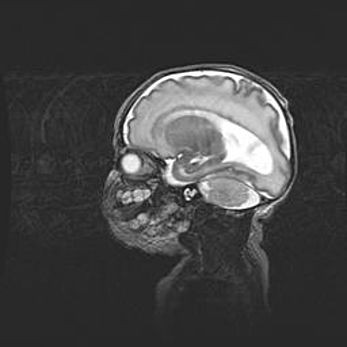

Лейкомаляция с кистозно-глиозной дегенерацией головного мозга.

Возраст: 2 месяца 25 дней

Вес: 6400 г

Окружность головы: 40 см

Срок гестации: 41 неделя

Лейкомаляцию относят к ишемически-гипоксическим повреждениям головного мозга, диагностируемым у новорожденных. При лейкомаляции в головном мозге обнаруживают очаги некроза, возникшие после тяжелой гипоксии и нарушения кровотока. В процессе морфогенеза очаги проходят три стадии: 1) развития некроза, 2) резорбции и 3) формирования глиозного рубца или кисты. Перивентрикулярная лейкомаляция (ПЛ) встречается примерно в 12% случаев среди новорожденных, обычно – у недоношенных детей, причем, частота ее зависит от массы, с которой младенец появился на свет. Наибольшее число малышей страдает лейкомаляцией, если масса при рождении 1500-2500 г.